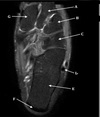

(178 cards)

1

Q

What is letter A?

A

SUPRASPINATUS TENDON

How well did you know this?

2

What is letter B?

ACROMION

Not at all

3

4

5

Perfectly